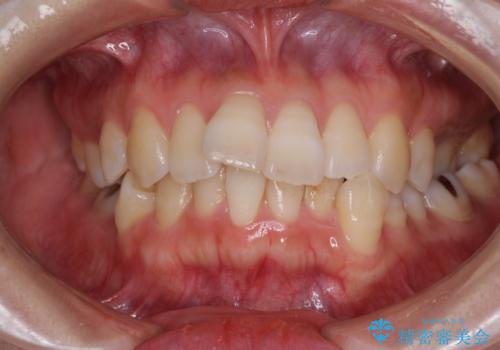

[インビザライン ライト] 短期間(3.5ヶ月)で終わるマウスピース矯正

![[インビザライン ライト] 短期間(3.5ヶ月)で終わるマウスピース矯正の症例 治療前](https://seimitsushinbi.jp/wp/wp-content/uploads/2020/02/C3-500x350.jpg?v=1580813654)